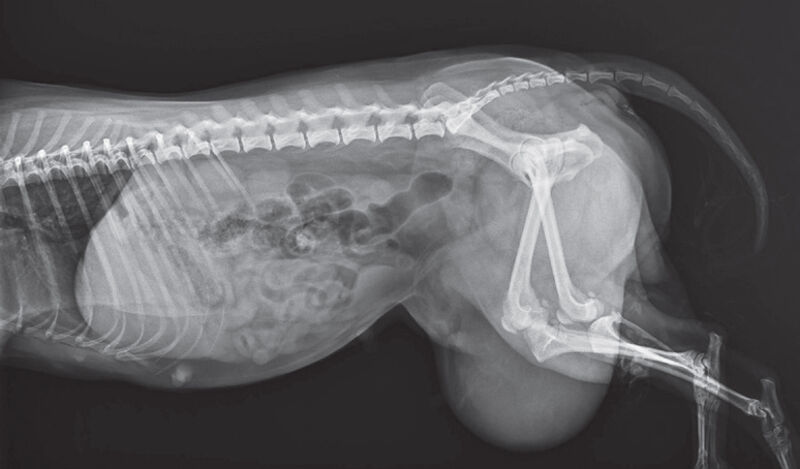

Röntgenvizsgálat során a magzat csontosodása nem volt látható, tehát még nem töltötte be a negyvenedik napot. Mivel kicsi volt a magzat és fejletlen, ezért az anya altatása és műtétje komoly veszélyt jelentett volna a kicsi életére. A műtétet viszont el kellett végezni, hiszen ha így marad, akkor a vérellátási gondok a növekedés során bekövetkeztek volna: a lágyékgyűrű strangulálta (megfojtotta) volna a magzatot, arról nem is beszélve, hogy a magzat növekedésével a duzzanat a talajig leérve a bőrt és a képletet sértette volna. A tulajdonos nagyon féltette a kis kedvencét, számára Ő a legfontosabb, azt kérte, hogy mentsük meg az életét.

A diagnózist követő másnap sor került a műtétre. A kiskutya altatása eseménymentes volt, azonban a műtét nem számított rutinbeavatkozásnak, és el is húzódott a technikai kivitelezés. A hasüreg megnyitásakor detektáltuk, hogy bár csak részben, de mind a két oldali méhszarv is belekerült a bal oldali lágyéksérv tartalmába.

Utólagos információként kiderült, hogy egy másik ivaros kan yorkshire terrierrel van együtt tartva. A tüzelés pár hete fejeződött be. Egyszer volt csak alom évekkel ezelőtt a párosításból, de mivel idősödött a nőstény, ezért úgy gondolták, hogy már nem is lesz alom többet. Azonban a biológia néha csodákra képes! Most is így történt. A hatéves szuka vemhesült, és a fejlődő magzat a méhszarvval együtt kicsúszott a lágyékcsatornán át a has bőre alá. Vérkeringési gondot nem jelentett a helyzetváltozás, ezért a magzat fejlődött tovább, nem halt el.